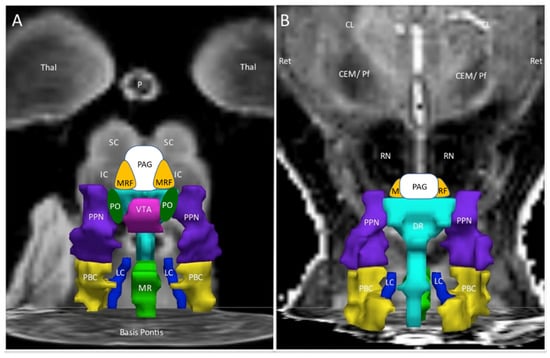

Figure 1.

Ascending arousal network. The original figure [37] in the coronal plane was annotated by adding periaqueductal grey (PAG, white), midbrain reticular formation (MRF, orange), and pontis oralis (PO, dark green). (A) The anterior view showed the ventral midbrain with posterior thalamus (Thal) as a “ceiling”, the superior (SC) and inferior colliculi (IC) as the backdrop, and Basis Pontis as the “floor”. (B) The posterior view of the dorsal midbrain was oriented to show the plane of the centromedian/parafascicular nucleus (CEM/Pf), reticular nucleus (Ret), and central lateral nucleus (CL) of the thalamus, pineal (P), and midbrain red nuclei (RN). This depiction suggested three layers with the MRF and PAG being most rostral. The middle layer contained the ventral tegmental area (VTA, violet), bilateral pontis oralis (PO, dark green), and pedunculotegmental nuclei (L and R PTN, formerly pedunculopontine nuclei and labeled PPN in the original image, navy blue) and dorsal raphe (DR, cyan) in the posterior midline. The caudal layer had median raphe (MR, green) and DR flanked by bilateral locus coeruleus (LC, navy blue) and parabrachial complex (PBC, yellow). The nuclei are contorted around white matter tracts that were not part of the original region of interest but constitute much of the ventral midbrain. The orientations of the nuclei displayed here do not align perfectly with the Paxinos histological atlas of the human brainstem [38].

The differential effects of exercise were summarized by the incremental changes between pre- and postexercise days (Figure 2). ΔBOLD was significantly larger (more positive, increased activation) for ME/CFS compared to GWI (negative change, diminished BOLD) in the midline PAG (periaqueductal gray), VTA (ventral tegmental area), DR (dorsal raphe), and MR (median raphe), bilateral PBC (parabrachial complex), PO (pontis oralis) and PTN (pedunculotegmenal nuclei, formerly pedunculopontine nuclei, PPN), and R_LC (right locus coeruleus). Controls had no net changes with exercise.

Incremental changes (∆) in the ascending arousal network nuclei. The red lines highlighted nuclei with significant exercise-induced incremental changes between postexercise and preexercise scans. ΔBOLD was significantly larger (more positive, increased activation) for ME/CFS compared to GWI (negative change, diminished BOLD) in the midline PAG, VTA, DR and MR, bilateral PBC, PO and PTN, and R_LC. Controls had no net changes. (A) is the anterior ventral view and (B) is the dorsal posterior view.

Significant differences in activation of the midbrain nuclei in the ascending arousal network (Figure 1 and Figure 2) have special implications for pain, negative emotion, and neurobehavioural dysfunction in ME/CFS and GWI [42]. Great advances have been made in learning the functions of this vital yet underappreciated organ. A review of each nuclear region provides a fresh perspective for interpreting the current results and generating new hypotheses for postexertional malaise, ME/CFS, and GWI.

This approach has multiple limitations. Echoplanar imaging, especially at the base of the skull, is susceptible to structural distortion and artifacts that require careful correction [31]. The brainstem moves with each breath and heart beat which requires gating by simultaneous electrocardiograms. It is a challenge to portray the three-dimension orientation of the nuclei in the usual plane of MRI scanning. As a result, the cartoon images (Figure 1 and Figure 2) must be interpreted with extreme caution. Even though the Harvard atlas was defined by histological and white matter tracing, the range of human anatomical variability makes it difficult to ensure that the seed regions were in fact congruent with the underlying averaged data from our previous fMRI analysis. The variability in overlap is apparent by comparison to other atlases that are also based on histological sections and 3T MRI scans of the brainstem [38].